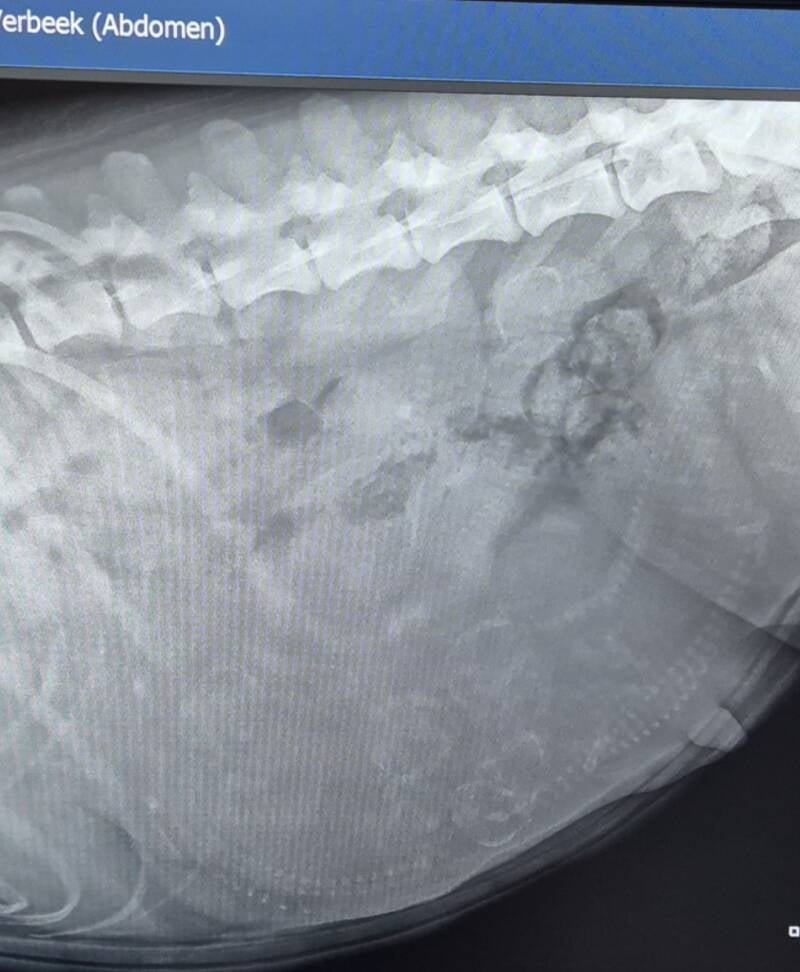

Maandag 13 mei 2024

Op de röntgenfoto zag de dierenarts vandaag 9 pups ! Het is geen hele goede foto, maar een paar ruggegraatjes/schedeltjes zijn er wel te zien :